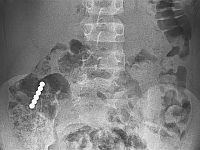

По словам доктора Самеха Татура, специалиста отделения детской и подростковой гастроэнтерологии, в больницу мальчик поступил в хорошем состоянии, у него не было ни рвоты, ни болей. В приемном покое ребенку сделали рентгеноскопию, показавшую несколько небольших магнитов, слипшихся в цепочку и находящихся в районе тонкого кишечника мальчика.

Мальчик был госпитализирован для наблюдения, вскоре выяснилось, что магниты застряли в зоне соединения тонкого кишечника и толстой кишки. Тогда было принято решение провести колоноскопию для извлечения магнитов. Операция проводилась под общим наркозом, врачам удалось обнаружить и извлечь магниты из кишечника ребенка, не прибегая к полостной операции.